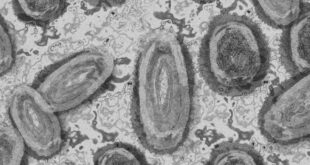

LEER MÁSDetectan primer caso de poliomielitis en Nueva York; el primero en 30 años

Un caso de poliomielitis fue detectado en Nueva York, este es el primer contagio de la enfermedad en los últimos 30 años. Nueva York confirmó su primer caso de poliomielitis detectado en una persona de los suburbios de la ciudad, este es el primer caso de la enfermedad en los …